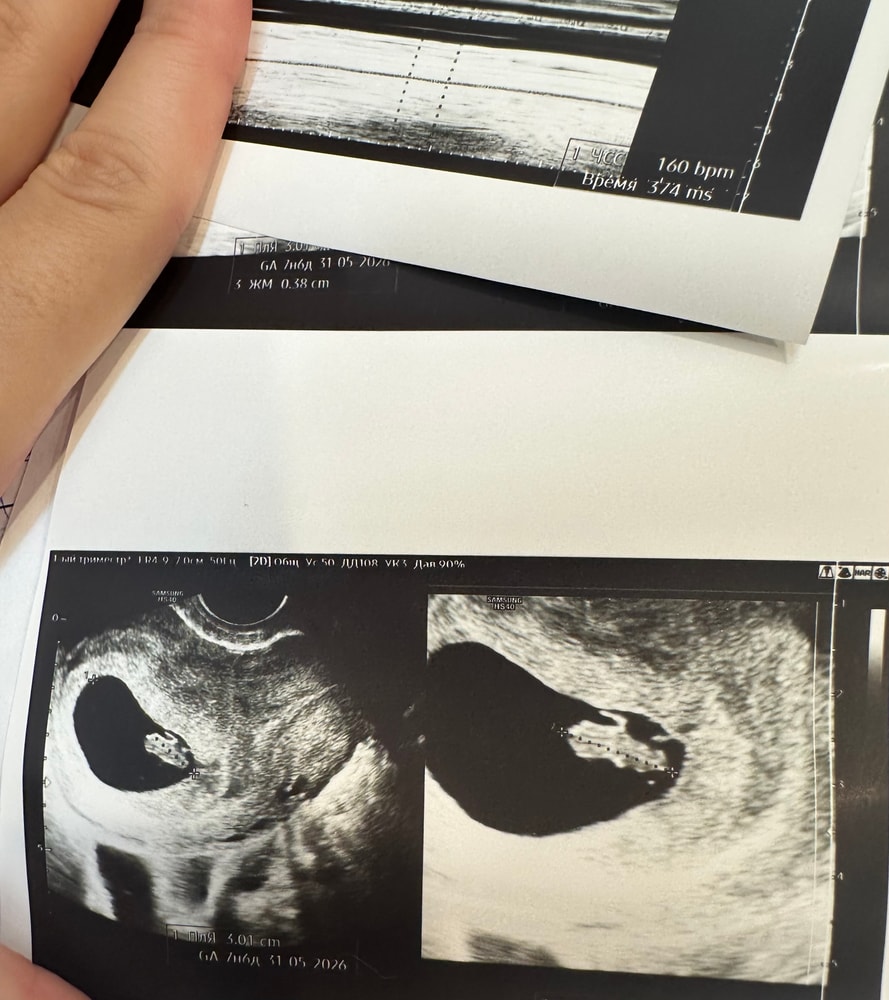

Наш маленький человек♥️УЗИ 7+5

Сходили мы на узи в 7+5 посмотреть нашу крошку перед постановкой на учёт))

ПЯ: 30мм

КТР: 13мм

Желточный мешок: 3,8мм

Сердцебиение: определяется четко, 160 уд/мин♥️

P.S Не понимаю,что там за отросточек?Неужели это уже ручка?🙈